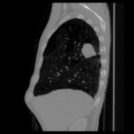

Aside from quantitative results, we provide a principal component analysis (PCA) visualisation of the 3D embeddings of Merlin, CT-FM, CT-CLIP, and our COLIPRI-CRM encoder, on a lung cancer case from the MSD Lung dataset (Fig. 1). The embedding resolution is very low for Merlin and CT-FM, providing hardly any semantic localisation. CT-CLIP yields embeddings of higher resolution, allowing features to be visually mapped from the input CT to the PCA map. However, the PCA map is inconsistent and noisy, and exhibits a strong bias towards absolute position within the scan, as visible through the anteroposterior green/red shift. On the other hand, our COLIPRI encoders yield higher-resolution embeddings, which are sharper and more consistent, allowing for clear recognition of the boundaries of the patient, lungs, and the abdominal organs, as well as the lung mass present in the right lung (on the left-hand side of the coronal and axial slice views).